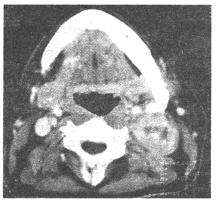

男,20岁,头痛、鼻塞、鼻出血,CT如图所示,最可能的诊断是()

A.鼻咽癌

B.巨大的鼻息肉

C.鼻咽纤维血管瘤

D.鼻咽神经纤维瘤

E.鼻咽腺样体增生